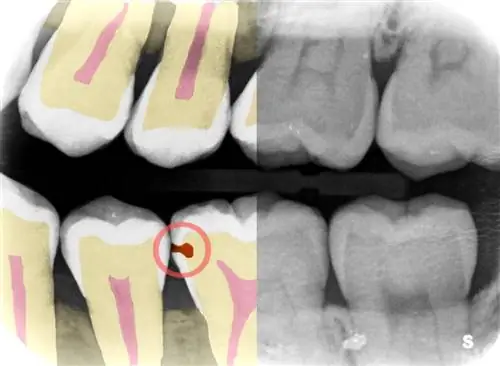

Предоставляя точку зрения более опытного стоматолога, Adra намерена сделать каждого дантиста «суперстоматологом», - сказал Фешараки TechCrunch. Его программное обеспечение выявляет кариес и другие проблемы с зубами на рентгеновских снимках зубов быстрее и на 25% точнее, поэтому клиники могут использовать это время для лучшего обслуживания пациентов и увеличения доходов.

«Мы исходим из опыта опытного стоматолога, чтобы помочь проиллюстрировать проблемы, превратив рентгеновские снимки в изображения, чтобы лучше понять, что искать», - добавил он. «В конечном счете, последнее слово остается за стоматологом, но мы привносим элемент опыта, чтобы помочь им сравнить и дать им рекомендации.”

Быстро указав на проблему и ее масштабы, стоматологи могут решить, каким образом они хотят ее лечить - например, поставить пломбу, провести лечение фтором или подождать.